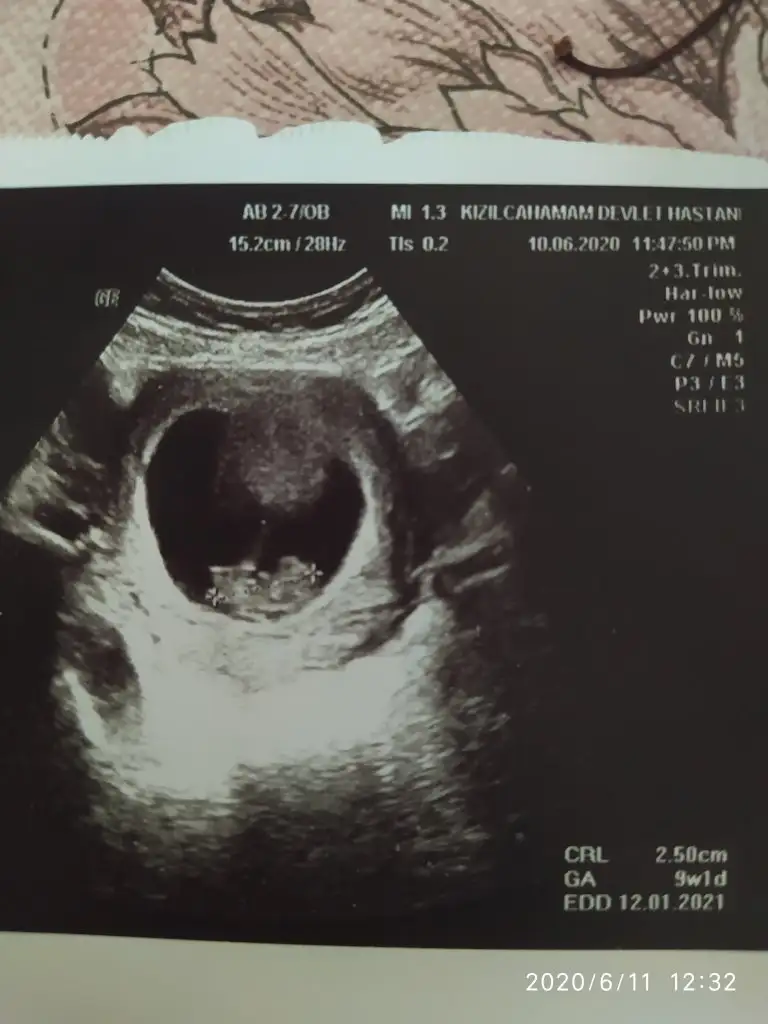

Başka usg varsa paylaşın sanki kız emin olamadımMerhaba bebeğimiz göstermedi bize cinsiyetini donuverdi arkasını 12+3 haftalık bi tahminde bulunabilir misiniz

Net değil kaç hafta usg 11 12 13 hafta olmalı emin olamadım tekrar usg paylaşınMerhaba, belli mi arkadaşımın bebeği Eki Görüntüle 2645769